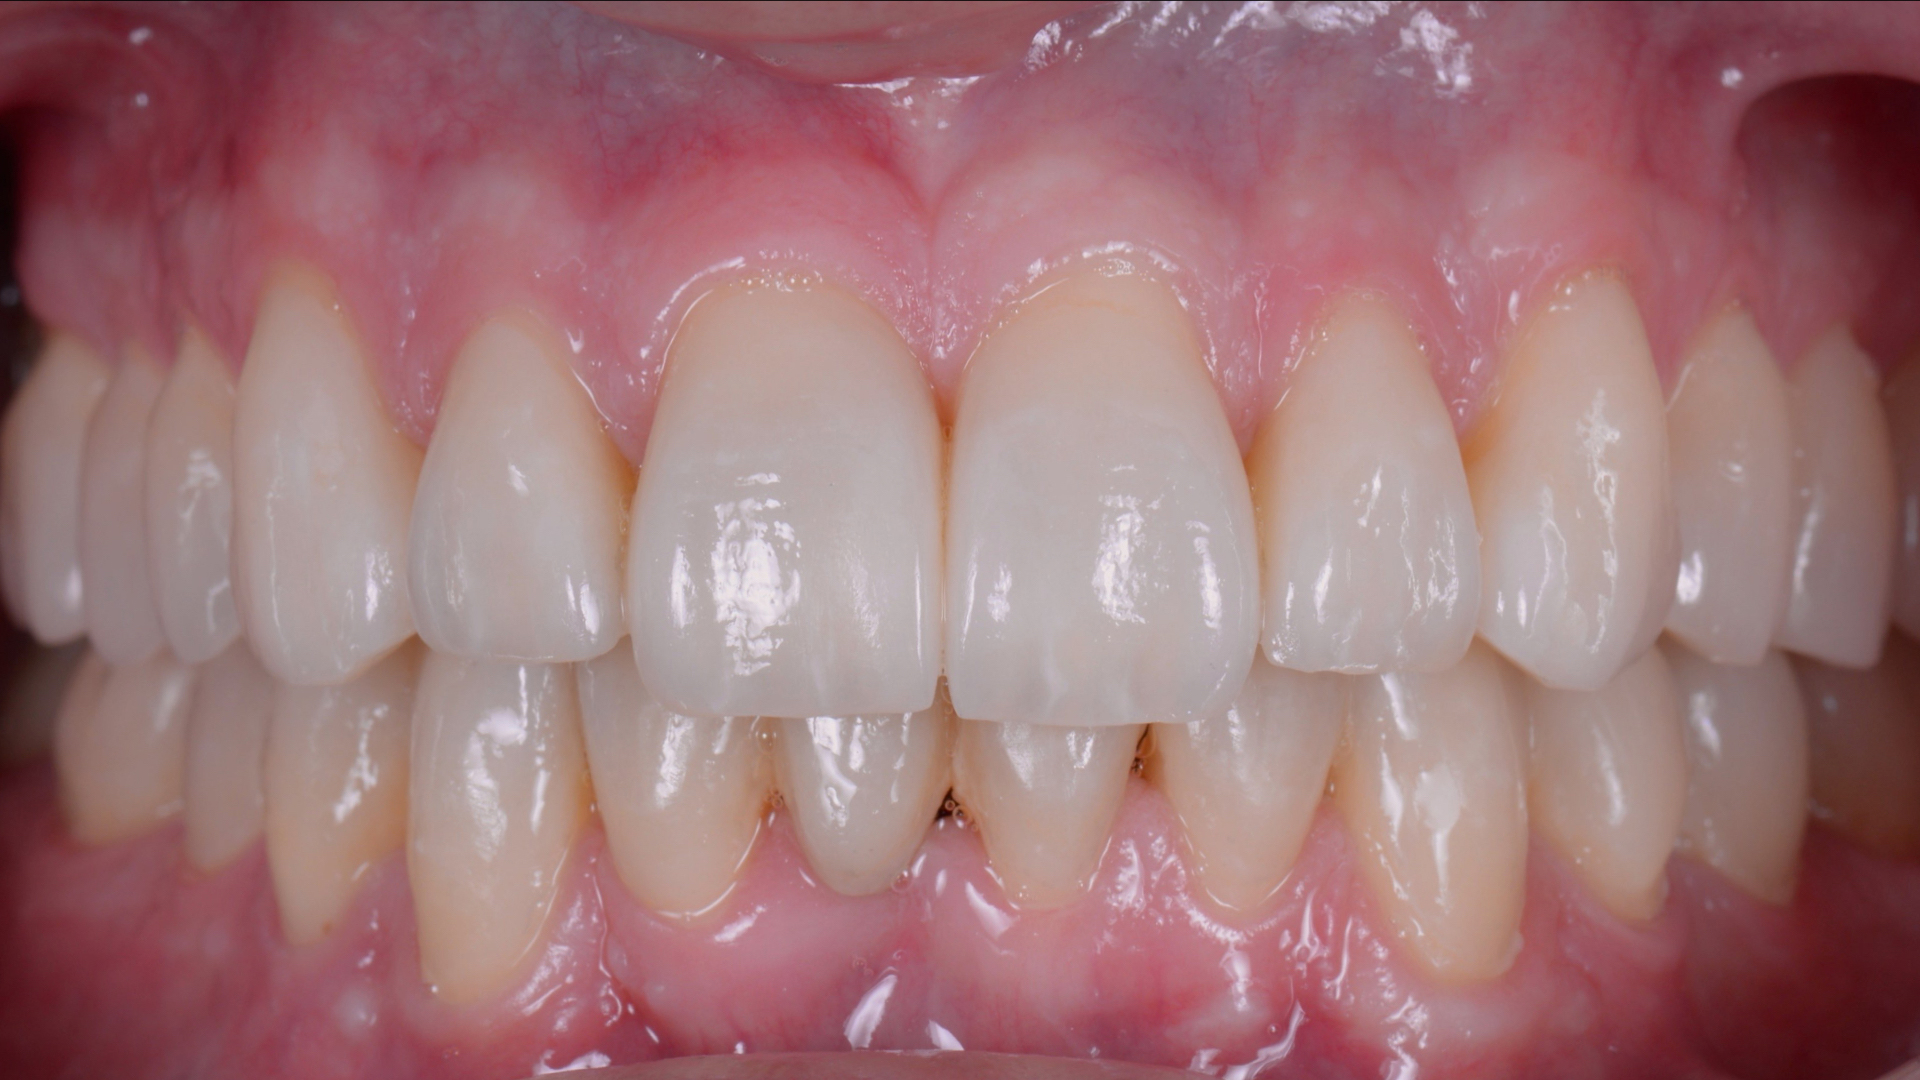

În situaţia de faţă, condiţiile au fost foarte bune pentru un tratament complet, minim-invaziv. S-au putut pune faţete dentare fără a șlefui dinții. Acest fapt s-a datorat în mare dimensiunilor dinţilor, dar şi spaţiilor existente între aceştia.

Putem spune că zâmbetul final este uluitor, iar acest fapt a dus la o creştere a încrederii în sine, dar şi a admiraţiei faţă de dr. Bâldea, care a ajuns să fie mentorul lui Giacomo, la vremea respectivă student la stomatologie, iar în prezent membru al echipei de specialişti ai clinicii noastre.